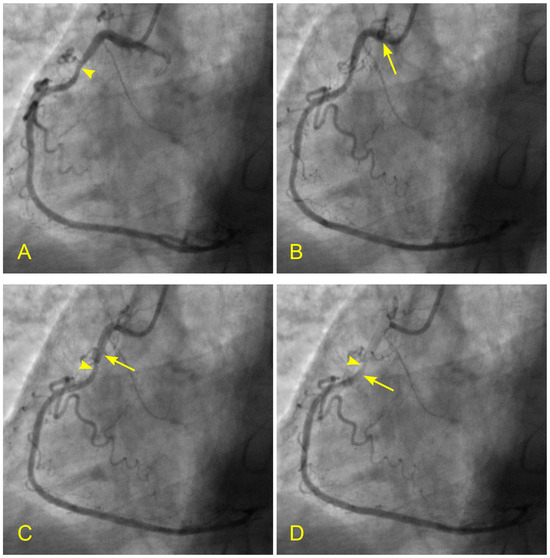

Figure 16.

(A,B) Blood flow across a coronary lesion. These images are in continuous sequence. A middle-aged patient presented with unstable angina and underwent a coronary angiogram. (A). The artery was full of contrast in black. There was a 50% lesion in the mid-segment of the right coronary artery (RCA) (arrowhead). (B) At the ostium of the RCA, the blood, in white, moved in at the beginning of diastole (arrow). (C,D) The blood flow across a coronary lesion. (C) The blood, in white, was now at the beginning of the RCA mid-segment (arrow) (D). The flow of white blood passed the lesion section quickly without disorganized flow (turbulent flow) (arrow). The location of the lesion is marked with an arrowhead. (E,F) The blood flow across a coronary lesion. (E) The blood, in white, was now at the end of the RCA mid-segment (arrow). There was no reversed flow at the lesion site (arrowhead). (F) The flow of white blood entered the distal segment without disorganized flow (turbulent flow, arrow) at the lesion site (arrowhead).